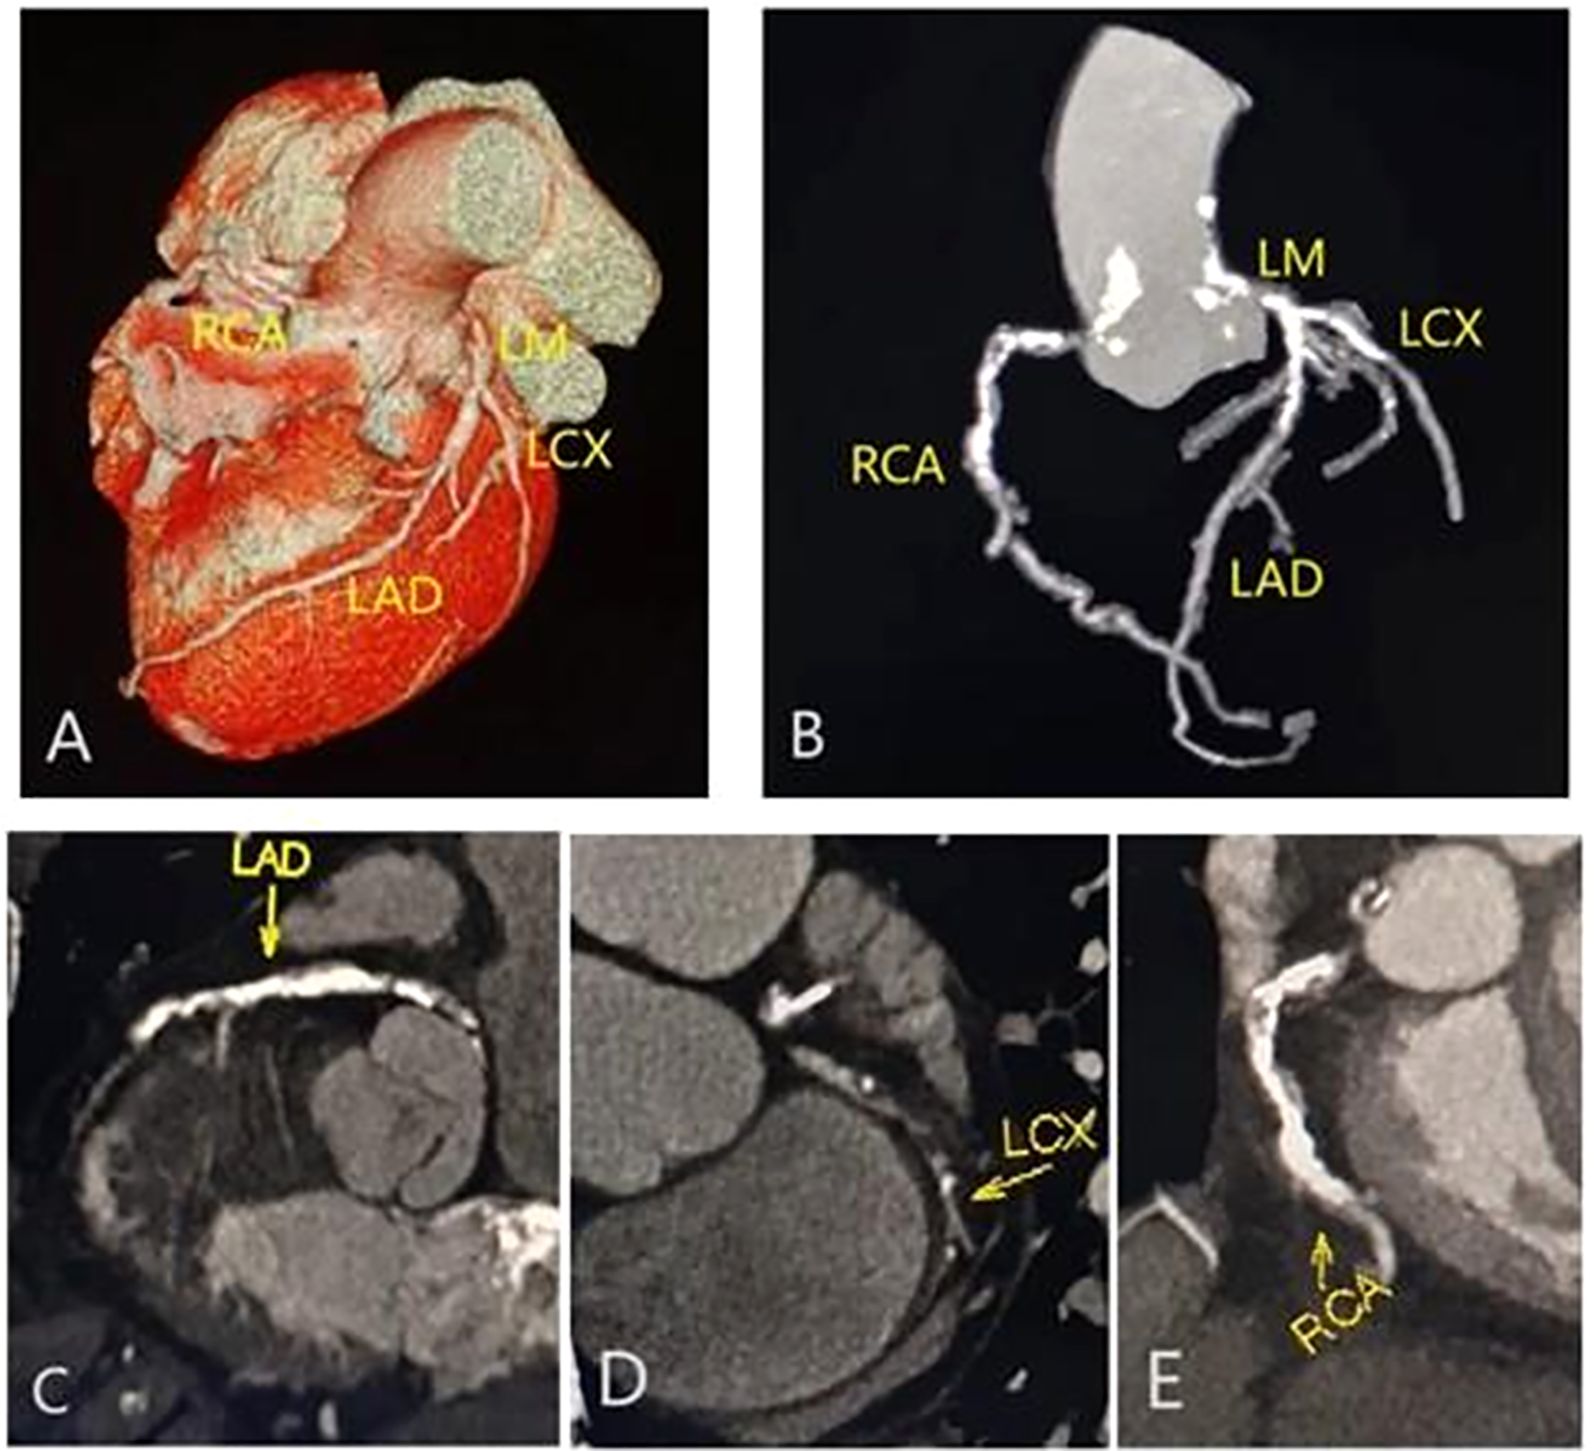

The image consists of five medical illustrations labeled A to E, showing different views of coronary arteries. Panel A displays a 3D model of a heart highlighting the RCA, LM, LCX, and LAD arteries. Panel B shows a schematic diagram of the same arteries. Panels C to E are detailed cross-sectional scans focusing on individual coronary arteries: C on LAD, D on LCX, and E on RCA, each labeled accordingly.

Figure 2. |Representative CCTA images of multivessel disease in a male with type 2 diabetes mellitus and metabolic syndrome. Volume rendering image (A); maximum intensity projection (MIP) CT image (B); and curvature plane reconstruction images (C-E) show the non-smooth edges, diffuse calcified, and mixed plaques of the LM, LAD, RCA and LCX.